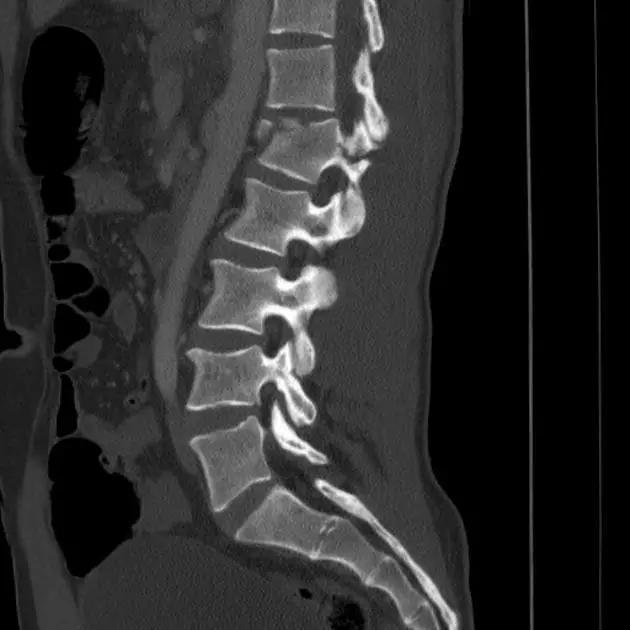

3. Chance 骨折

胸腰段椎体的分离性骨折,伴随脊髓、神经根、椎体的水平方向的崩裂骨折。又称座带骨折(seatbelt fracture)。

由 Chance 于 1948 年首先描述此骨折,故文献又常称 Chance 骨折,为一种屈曲拉伸骨折。典型的损伤机制为汽车座带束于患者腰腹部,当高速行驶的汽车突然减速或撞车时,座带支点以上的躯干屈曲,前冲力还同时产生一个向前拉伸的力量。将椎体由后方向前撕裂,骨折线横过椎体、椎弓根和椎板,椎体后部的韧带完全撕裂。有时前纵韧带亦可撕裂,常合并有神经系统的症状。

(来源:Radiopaedia)